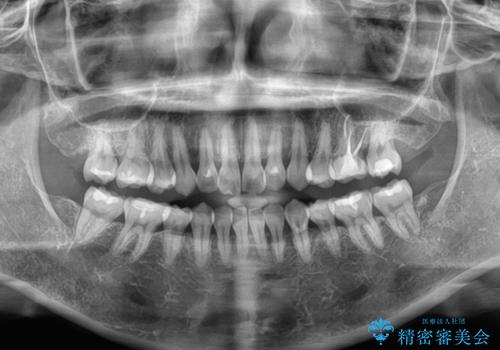

- 上下前歯の後戻りを気にして来院された患者様です。

インビザラインでの治療を希望されていて、デコボコの程度が中等度であり、安価なパッケージにて対応可能と判断されたため、インビザライン・モデレートを用いて矯正治療を行うこととしました。